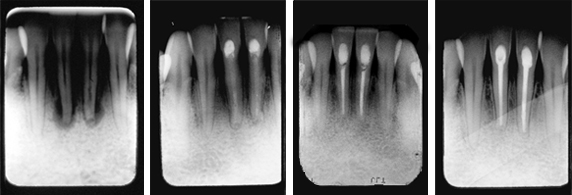

Routine Treatment Between Office Visits

- For routine use as an intracanal dressing between office visits to cleanse the canal.

- pH > 12 cleanses canal

Treatment of Complicated Cases

- For complicated cases involving traumatic injury and other instances where extended calcium hydroxide therapy is indicated.

- Treats periapical lesions, abscesses, traumatic injuries, root resorption, root perforations, and weeping canals

- Stimulates apexification and apexogenesis